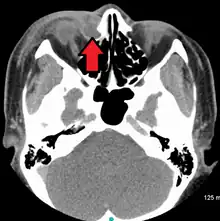

| A case of dacryocystitis as seen on CT scan | |